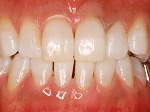

術前

→

術後